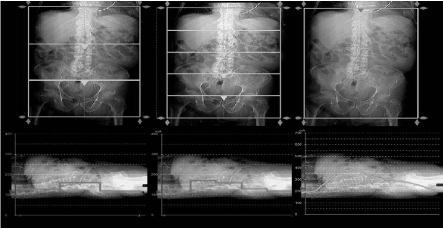

We observed that the automated tube current modulation was less precise with the WV mode than with the helical mode. (Figure 2)

Figure 2. Results of tube current modulation with different collimations in Wide Volume mode (left. 3 volumes, middle: 5 volumes) and with the Helical mode (right).

The tube current modulation technique in the Z-axis used in routine clinical practice consists of modulating the tube current (mA) of the radiation in the Z-axis, depending on the density and thickness of the tissues to be acquired.

In helical mode, there is a very precise modulation, performed at every rotation, which reduces the dose by 43% to 66% when compared to acquisitions without modulation on abdominopelvic scans according to Kalra et al. [10].

The tube current modulation in Z-axis in WV mode is identical within each volume, but varies between 2 volumes acquired and could be problematic for areas with a high-density difference such as the shoulders-neck or pelvis [11]. Consequently, a smaller collimation in WV enables a better tailoring of the tube-current modulation, and drives a reduction in the radiation dose. In the study of Gervaise in 2010 [3], there was a difference of contrast between each volume, related to the difference of charge between them. This phenomenon was not observed on our radiosensitive films as well as in our clinical study where there was no inappropriate difference of contrast between the volumes (Figures 5, 6).